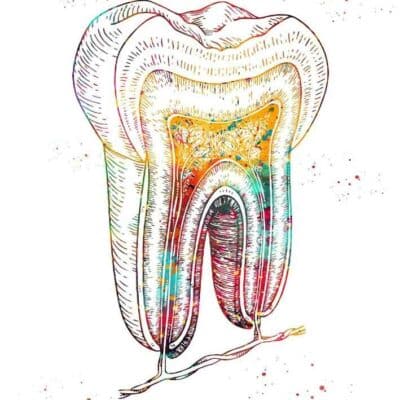

Tableaux murale pour la décoration intérieure d’un cabinet médical dentiste